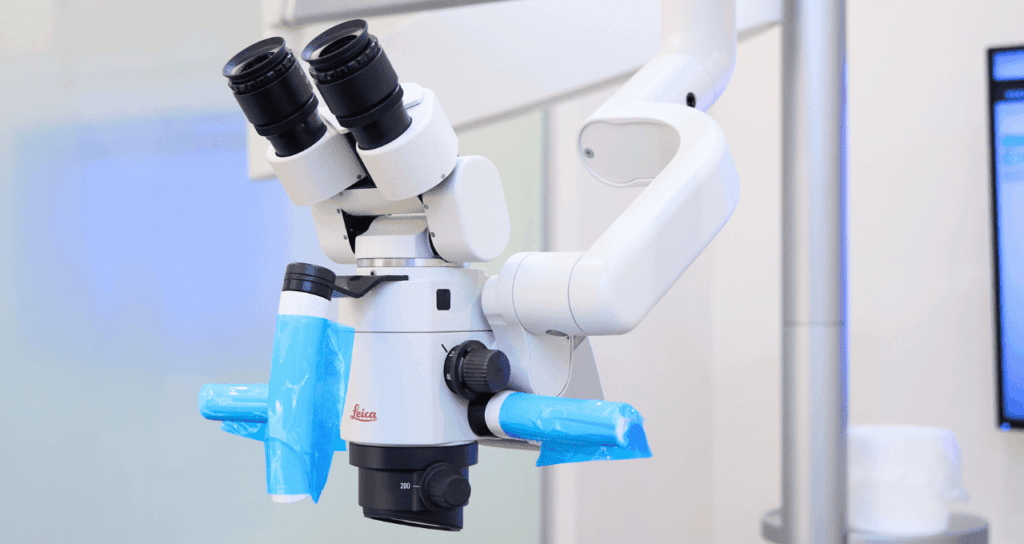

「見えない」を「見える」に変えるマイクロスコープ

当院の根管治療の最大の特徴は、歯科用マイクロスコープ(手術用顕微鏡)を導入していることです。

マイクロスコープは、肉眼の最大約20倍まで視野を拡大することができる装置です。

肉眼では単なる小さな穴にしか見えなかった根管の入り口が、マイクロスコープを通すことで巨大な洞窟のように鮮明に見えるようになります。

強力なライトで根の奥底まで明るく照らし出すため、以下のような微細な異常も見逃しません。

「見えている」からこそ、確実に汚れを取ることができる。

「見えている」からこそ、健康な歯質を削りすぎずに済む。

マイクロスコープの活用は、治療の成功率を飛躍的に高めるための必須条件です。